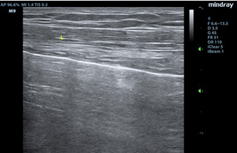

C1.  C2.

C2.

Figure C. Image C1 is a real-time scan of a normal lung with POCUS. Figure C2 is a CT scan of a patient who had a collection of some fluid in the chest.